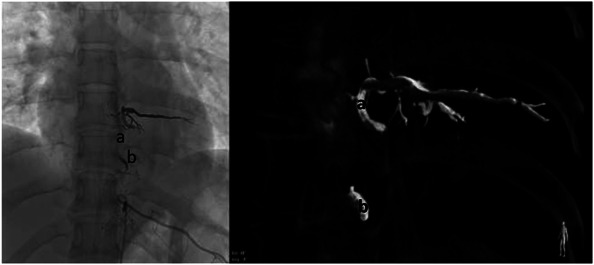

Clinical presentation: An adult patient who consulted about a 1 year and a half of flank pain refractory to analgesic management and hypoesthesia on palpation in the left T8 dermatome, therefore, pain of radicular origin was suspected. MRI of the thoracic spine was requested, showing an image suggestive of vascular malformation at the level of T8. After identification of the lesion, the patient was taken to spinal angiography to delimit the vascular malformation, finding an image suggestive of spinal venous vascular ectasia associated with a low-flow fistula of paravertebral location at T8. Subsequently, the case was discussed by a multidisciplinary team that established endovascular embolization as the best option for treatment. Thus, achieving complete occlusion of the lesion without complications and a slow improvement of the symptoms.